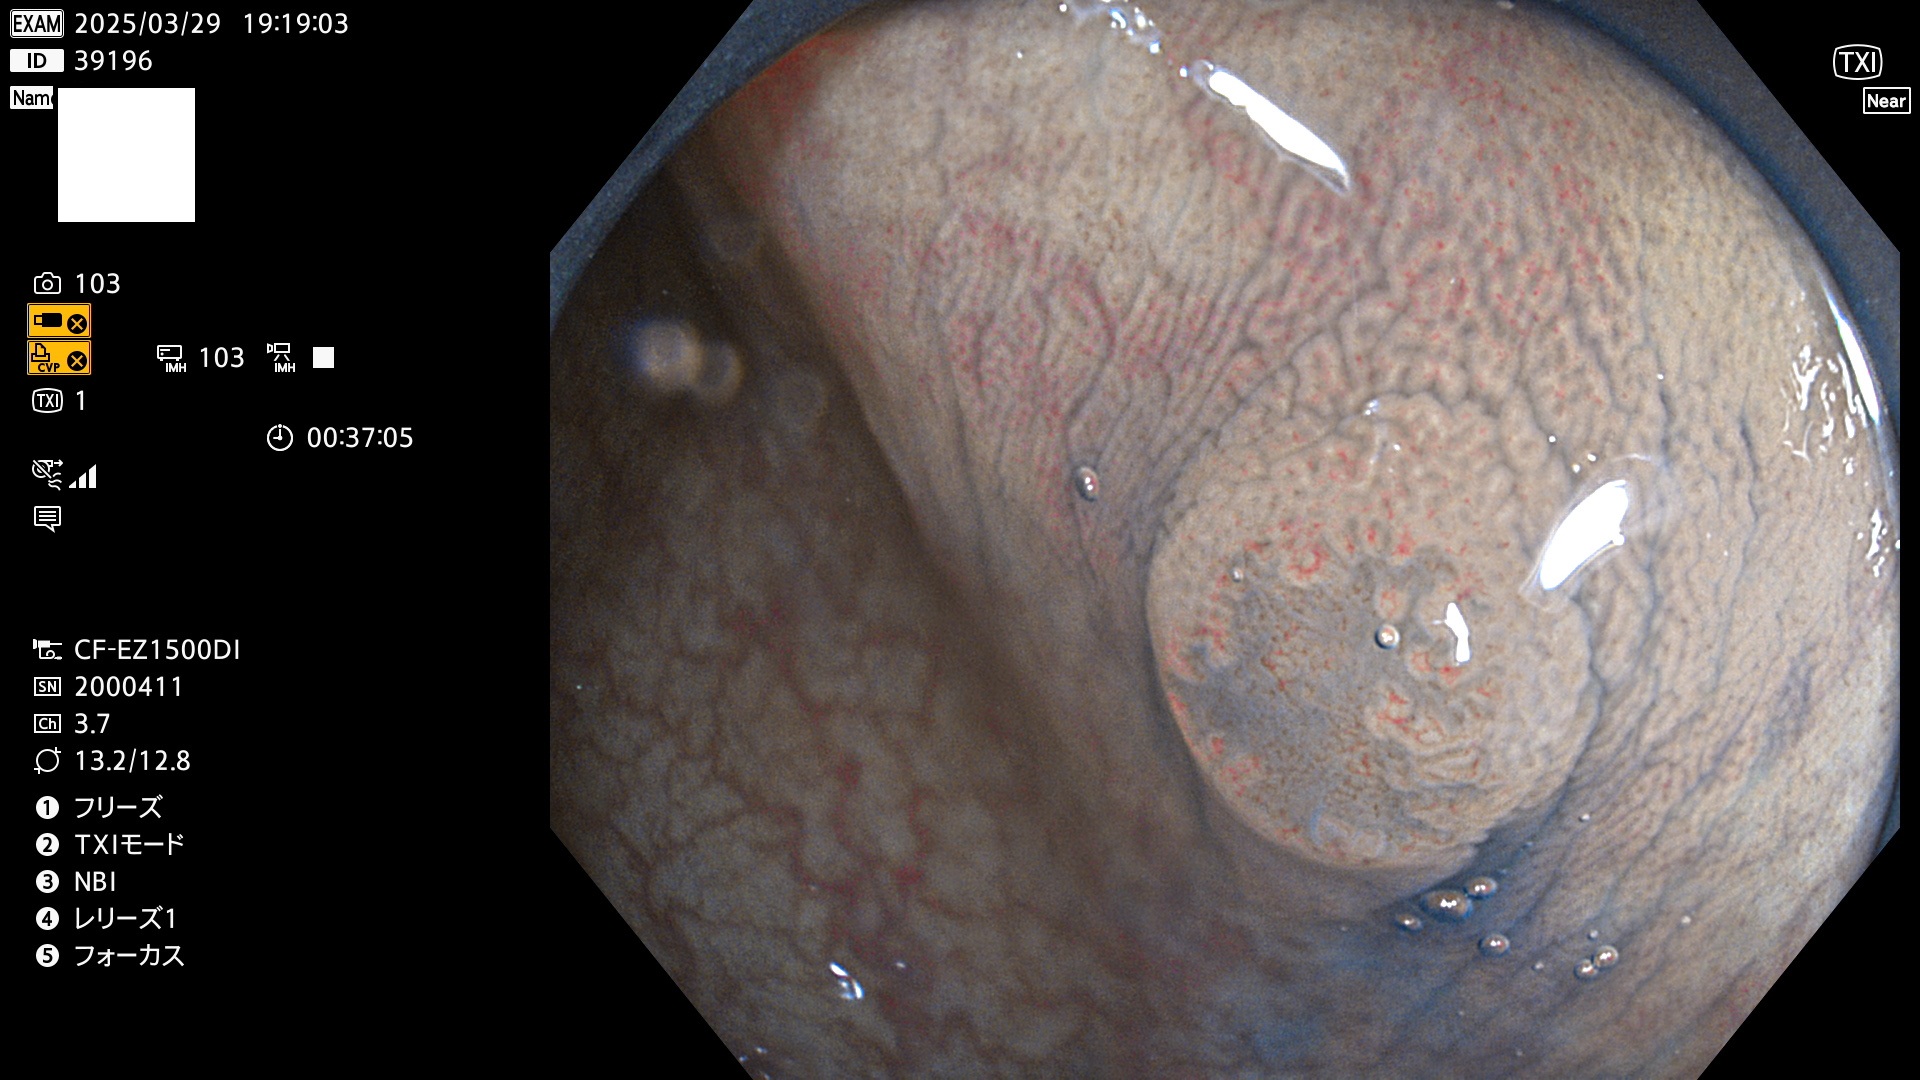

完全に平坦な物をUb、陥凹している物をUcと呼びます。Ubは認識が困難で、Ucはびらん(炎症)と紛らわしいために見落とされやすく、「内視鏡後・大腸癌」の原因になります。

抽出の対象期間 2025年3月27日〜3月30日の4日間(48件の検査)8個 (8/48=16%)